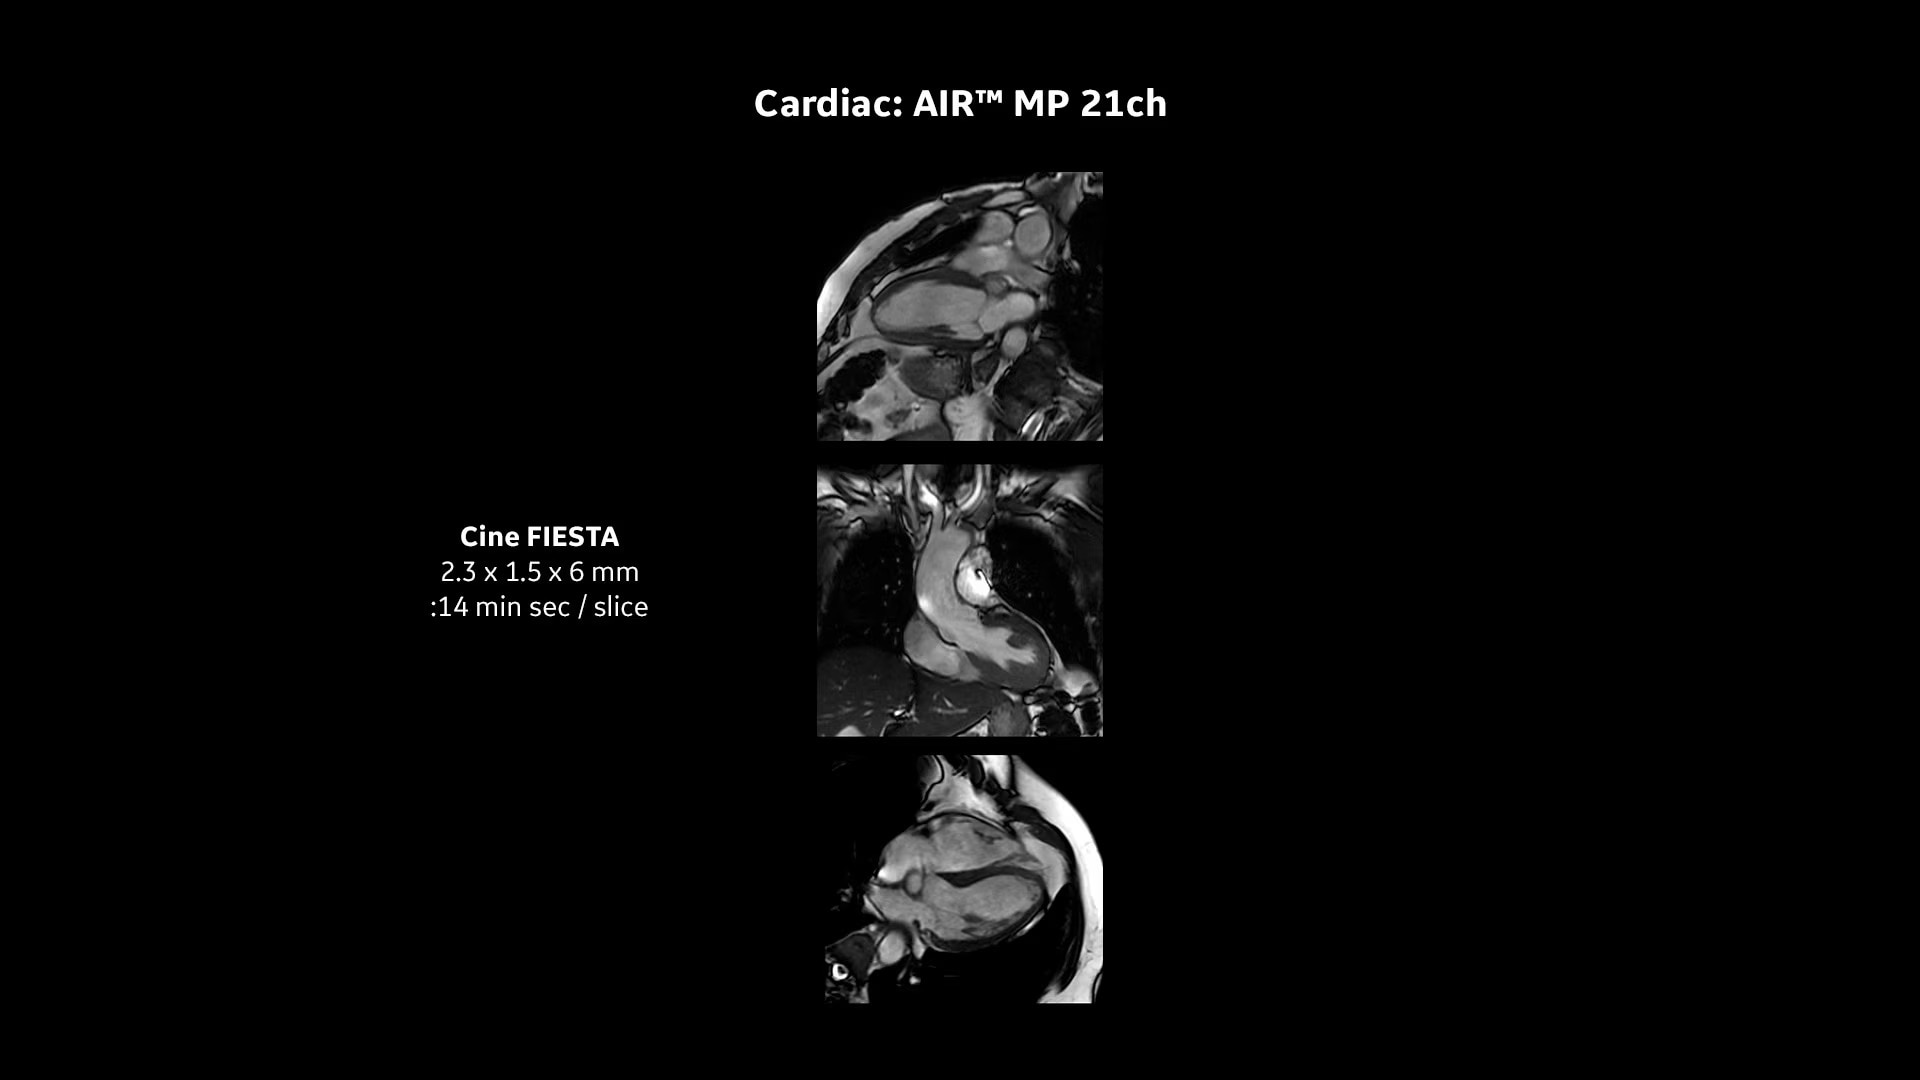

Every step of our cardiac MR assessment is compatible with our pioneering deep-learning algorithms, including: morphology, function, perfusion, mapping and myocardial viability with

late enhancement.

Your teams can capture clarity with AIR™ Recon DL, a revolutionary technique to boost image quality, providing accurate anatomic information and advanced soft tissue contrast. It’s already transformed the lives of millions of patients worldwide since 2021. Thanks to Sonic DL™ they can also now assess cardiac viability faster than ever before, with as little as 15 to 20 minutes per scan.*†